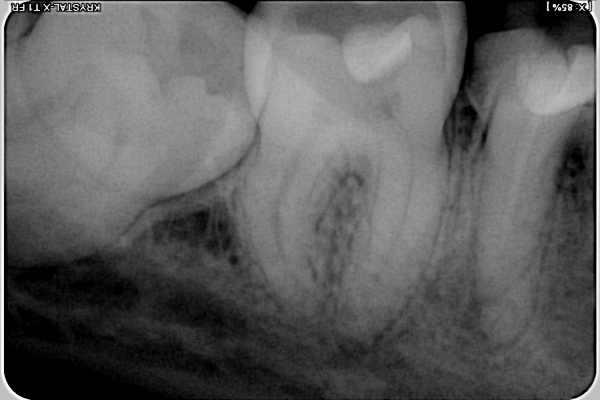

Беспокоят 2 зуба, точнее то, что один из них жевательная шестерка снизу сломалась, а на противоположной стороне отлетела пломба. По снимкам, один врач предложил удалить оба зуба, и поставить мосты. Другой врач предложил удалить только с одной стороны (36), а на другой (46) надеть коронку, но там у меня свищ.

Вам предстоит удаление и 3.6 и 4.6 зубов.

Нецелесообразно вкладывать деньги в зуб, в котором повсюду воспаление. Ни один врач, который вам действительно захочет помочь, не наденет на него коронку.